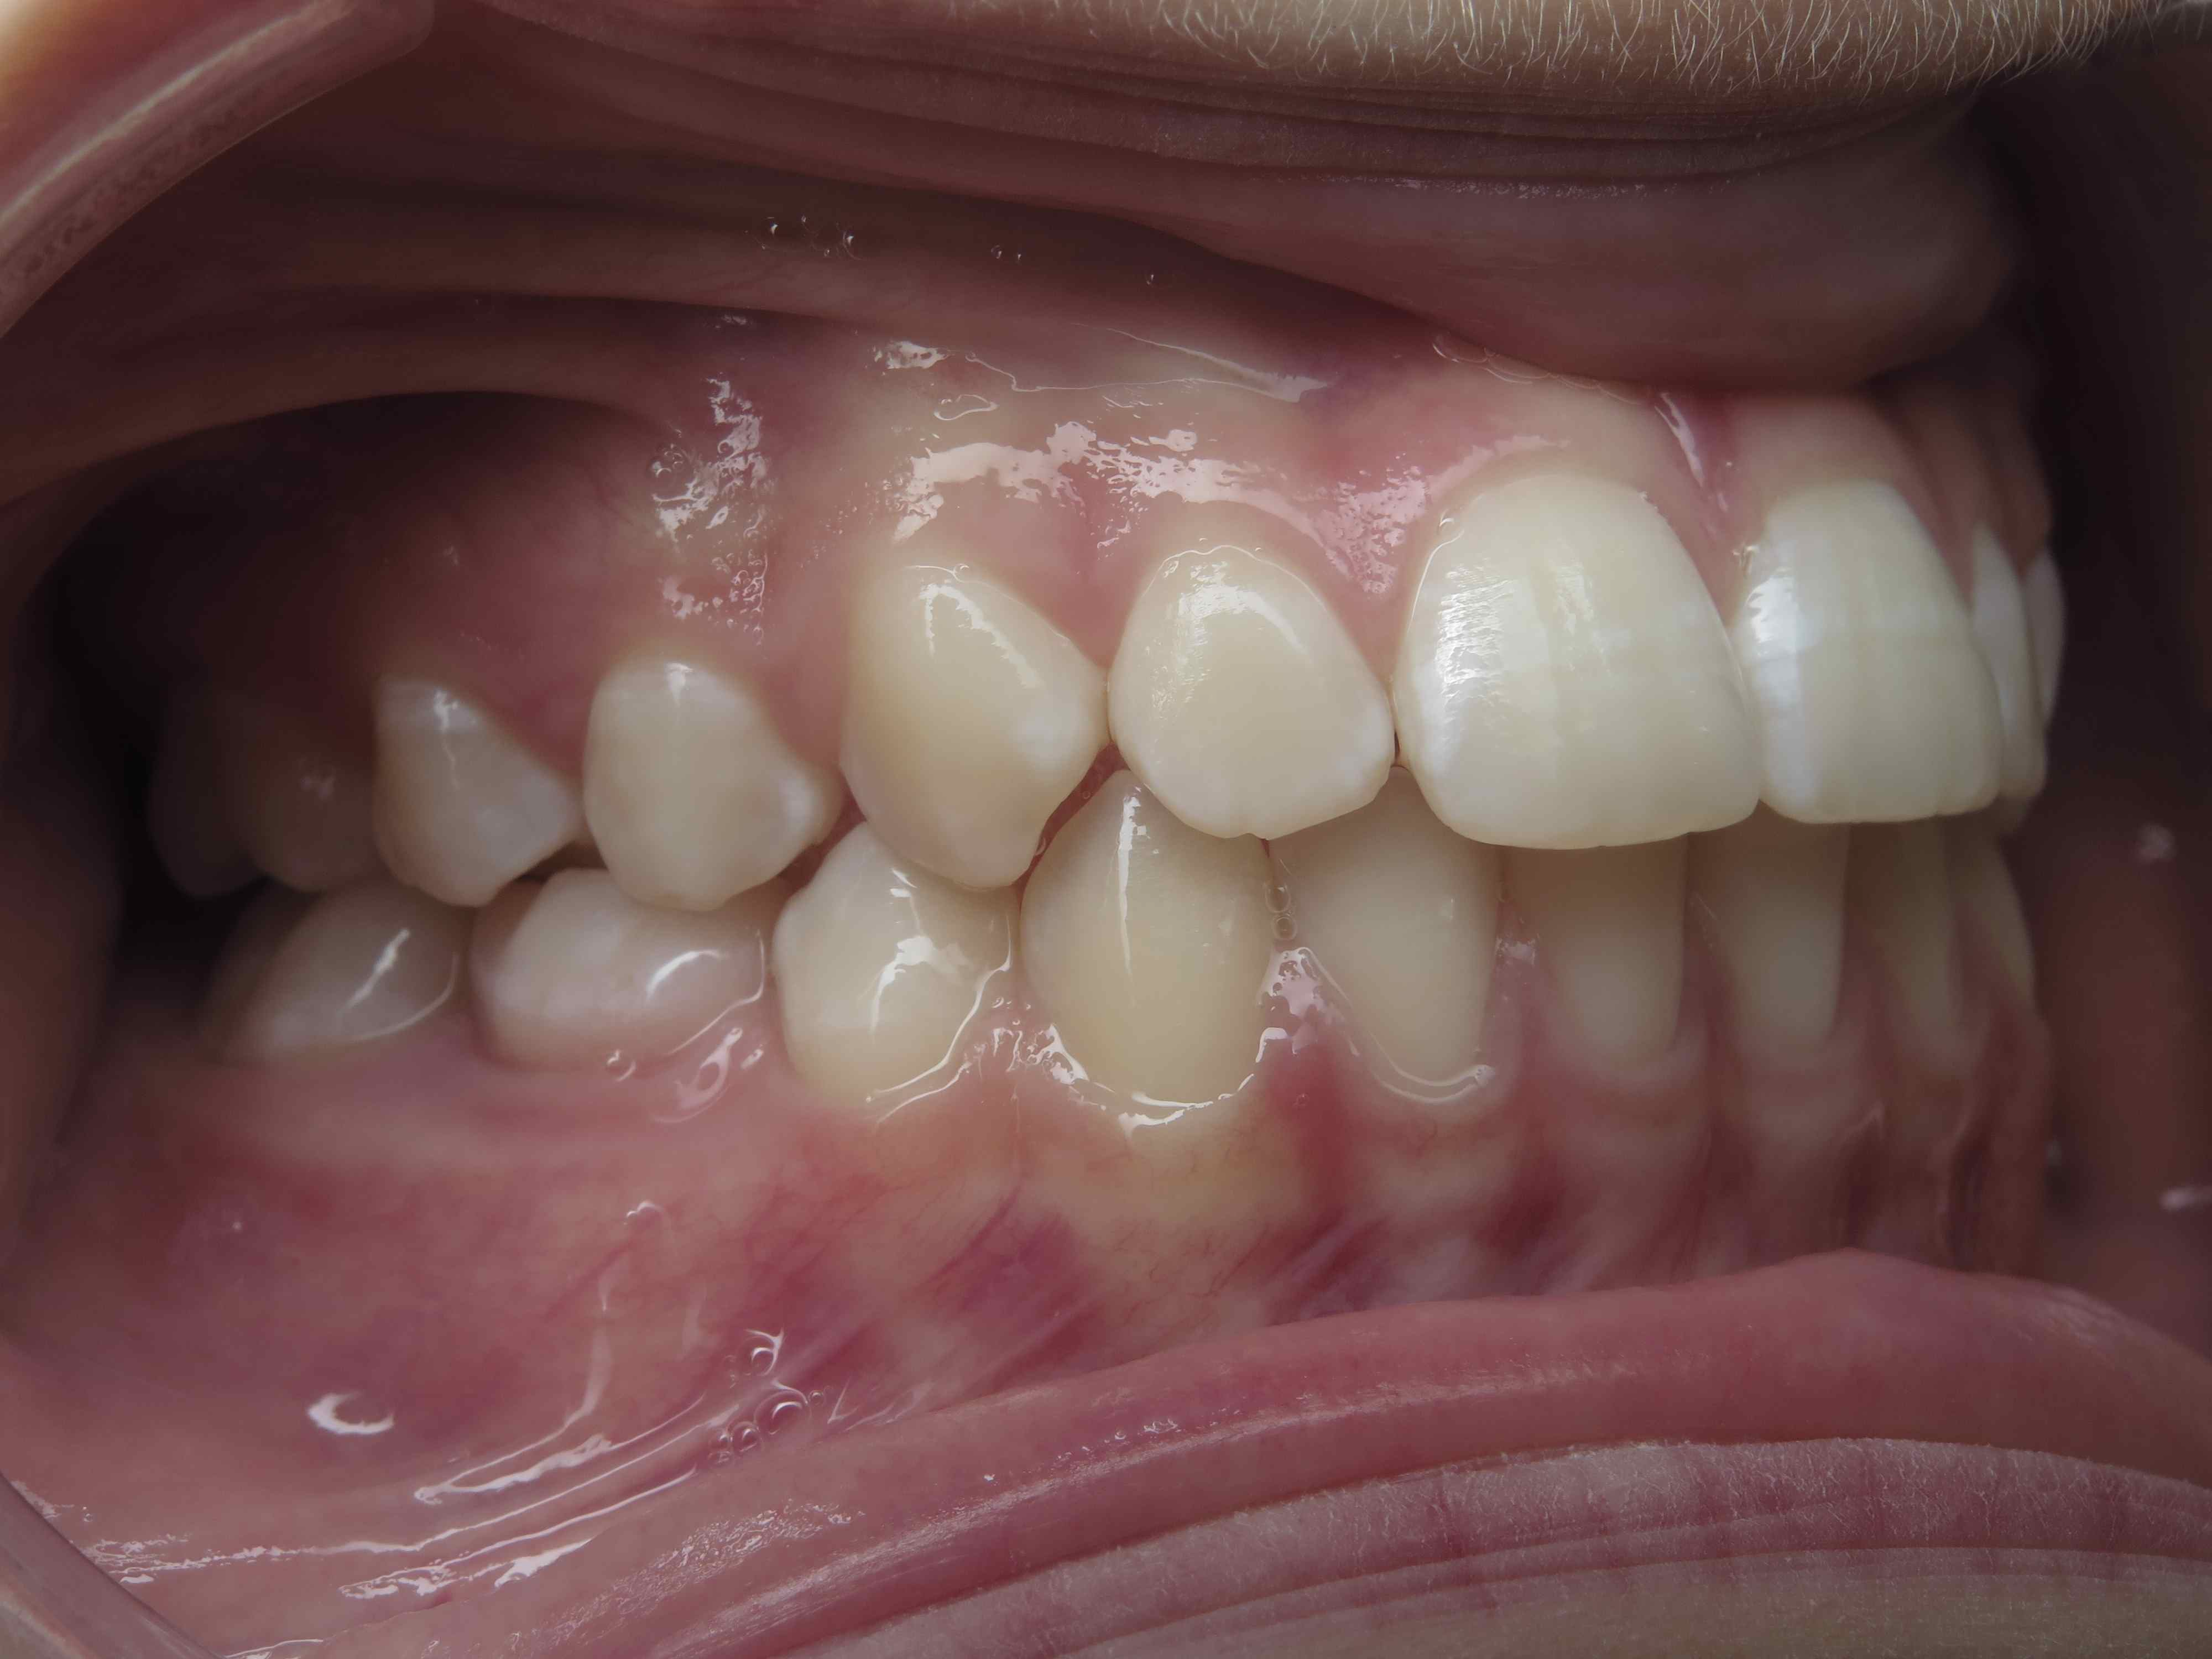

appareillage mobile pendant 35 mois

surveillance évolution de la dentition pendant 5 ans

appareillage multibagues traitement en cours

bilan début et en cours de traitement